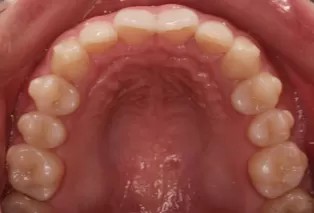

Intraoral photos